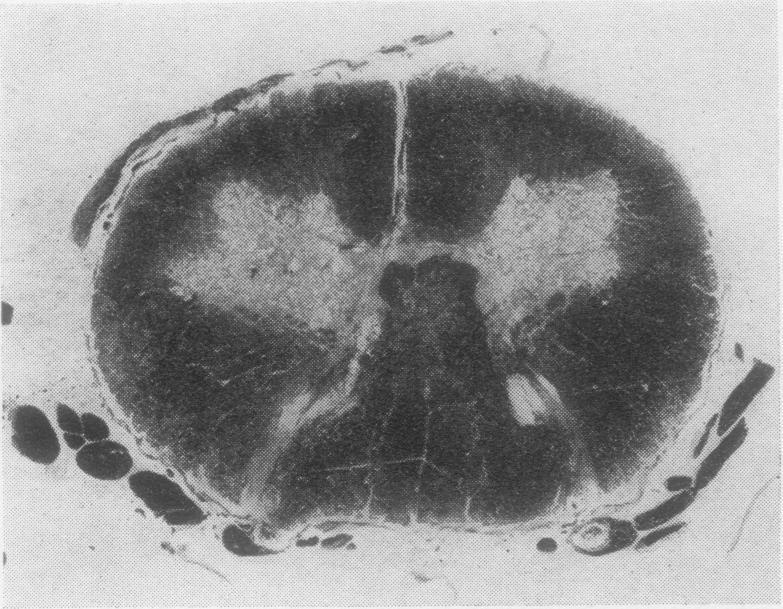

The clinical and pathological findings are described of a fatal case of acute haemorrhagic leucoencephalitis and disseminated encephalomyelitis with acute necrosis of the white matter of the spinal cord. It is suggested that the reaction was a severe immunological response of an allergic nature, probably due to antitetanus serum.